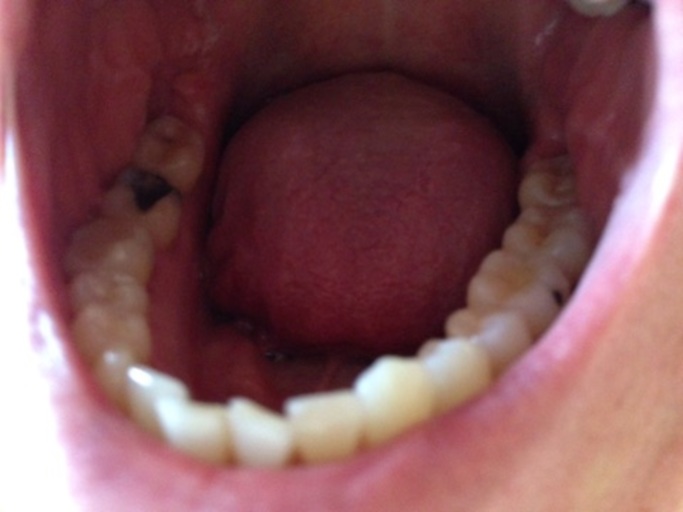

Is this a cavity in my wisdom tooth?

Hi, I am 31 and have observed a dark spot on my lower wisdom tooth (the tooth behind the one with the large silver filling on the picture). All my wisdom teeth have erupted quite good, but short after eruption I had small cavities which were filled...

Is the hole in my tooth a cavity or broken composite filling?

Hello, I have a question about my back molar on the bottom row. I have had white composite fillings as well as sealants in the past years ago. It appears I have a hole in my tooth and it looks as though the filling has broken leaving a nice sized...